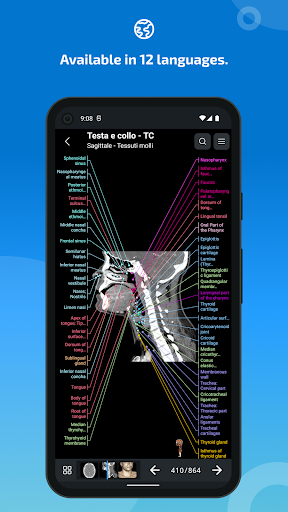

e-Anatomy tiene más de 26 000 imágenes que contienen series de imágenes en vistas axiales, coronales y sagitales, así como radiografías, angiografías, imágenes de disección, gráficos anatómicos e ilustraciones. Todas las imágenes médicas fueron etiquetadas cuidadosamente, más de 967 000 etiquetas disponibles en 12 idiomas, incluida la Terminologia Anatomica latina.

- Cambie de idioma con solo tocar un botón